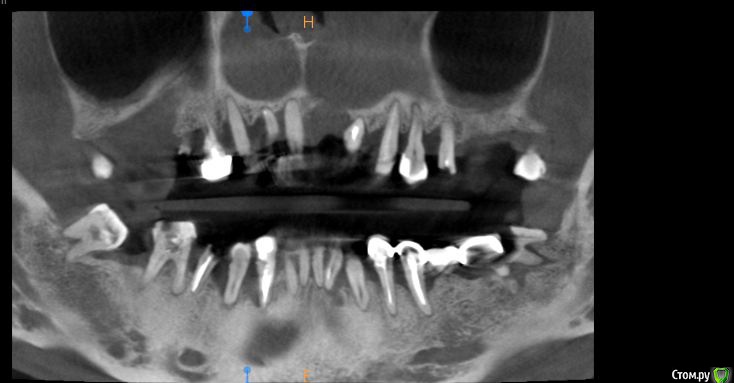

St. Опубликовано 17 апреля, 2018 Поделиться Опубликовано 17 апреля, 2018 Обзорные срезы ( верх, низ, топография нижнечелюстного нерва), дефект в обл 21 Ссылка на комментарий